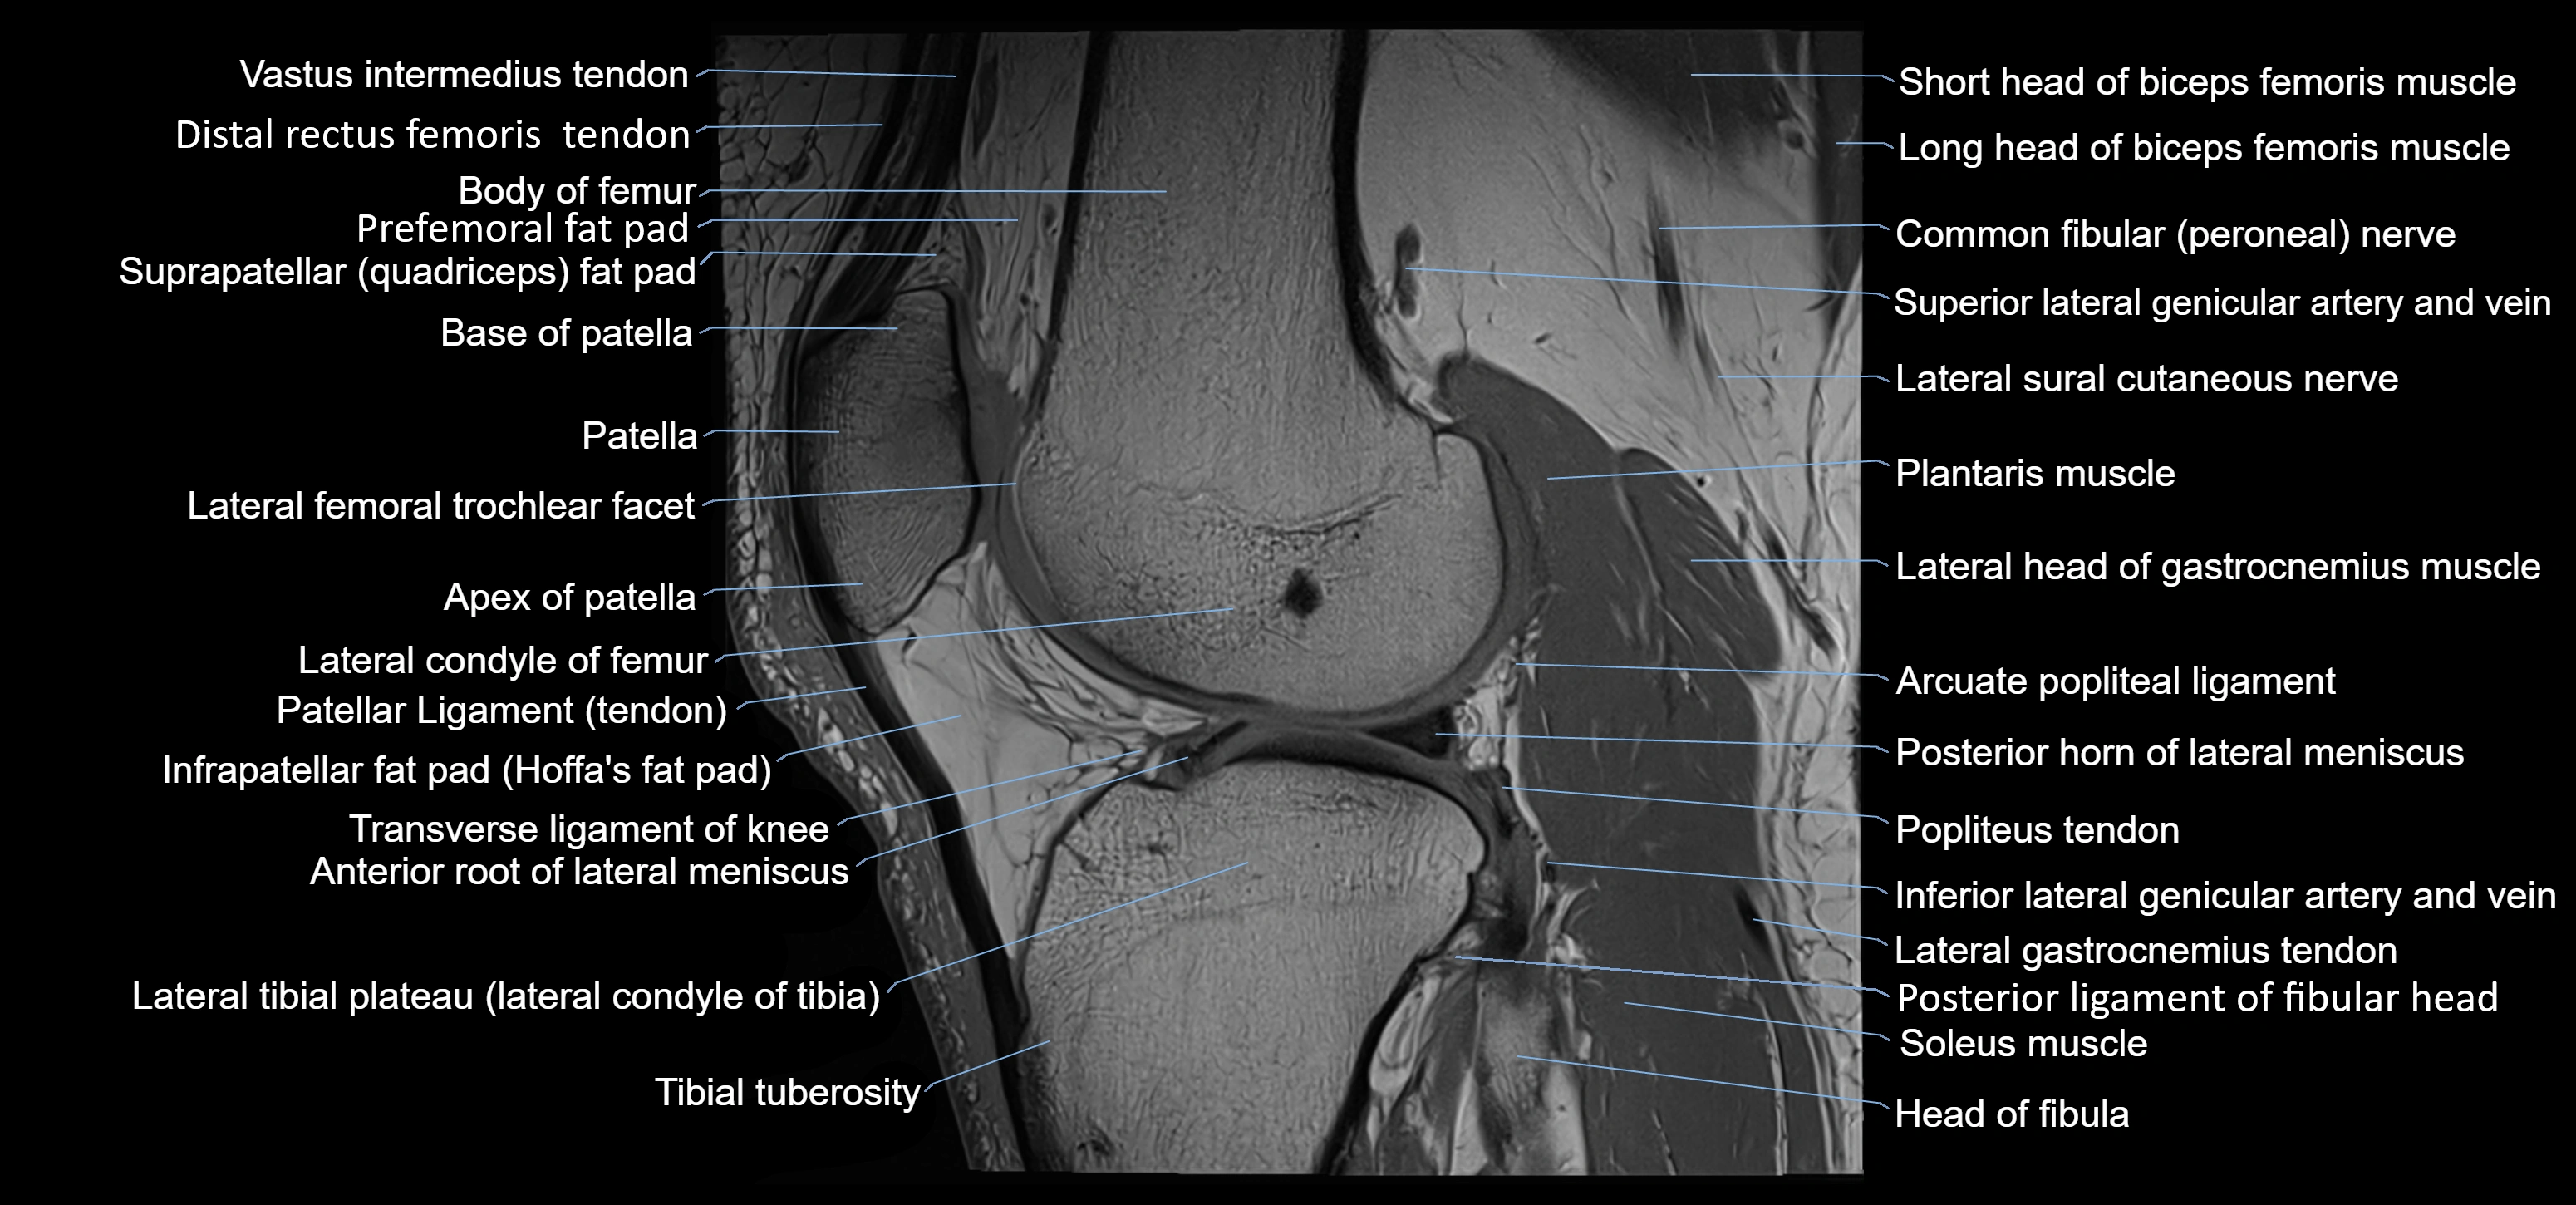

- Anterior root of lateral meniscus

- Arcuate popliteal ligament

- Distal rectus femoris tendon

- Distal vastus intermedius tendon

- Head of fibula

- Infrapatellar fat pad

- Lateral condyle of femur

- Lateral gastrocnemius tendon

- Lateral head of gastrocnemius muscle

- Lateral meniscus

- Lateral sural cutaneous nerve

- Patella

- Patellar articular cartilage

- Patellar tendon (patellar ligament)

- Plantaris muscle

- Popliteus tendon

- Posterior horn of lateral meniscus

- Posterior ligament of fibular head

- Prefemoral fat pad

- Soleus muscle

- Suprapatellar fat pad

- Tibial tuberosity

- Transverse ligament of knee